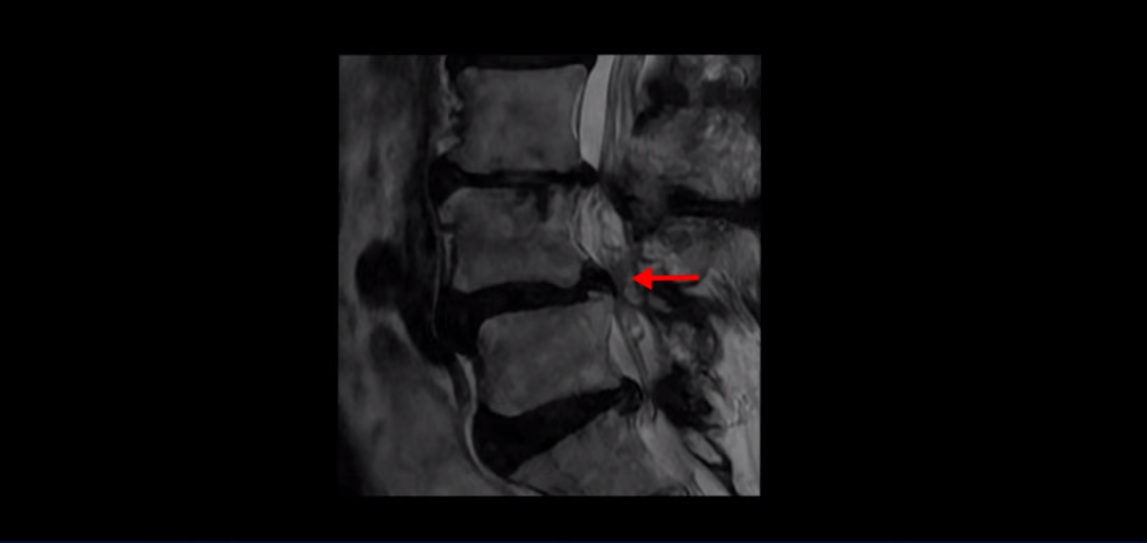

제가 먼저 이분 MRI를 보고 설명해 드린 후 어떻게 이런 분들을 수술 없이 허리 기능재활치료로 호전시킬 수 있는지 자세히 설명드리겠습니다. 이분 허리가 보시다시피 여러 마디가 퇴행되어 있고

4번 5번에는 뼈가 밀려 나간 전방전위증도 있습니다.

4번 5번 마디를 자세히 보면 심한 중심성 협착이 있어서 신경 구멍이 매우 좁아져 있습니다.

또 신경 가지가 빠져나가는 추간공도 매우 좁아져 있습니다.